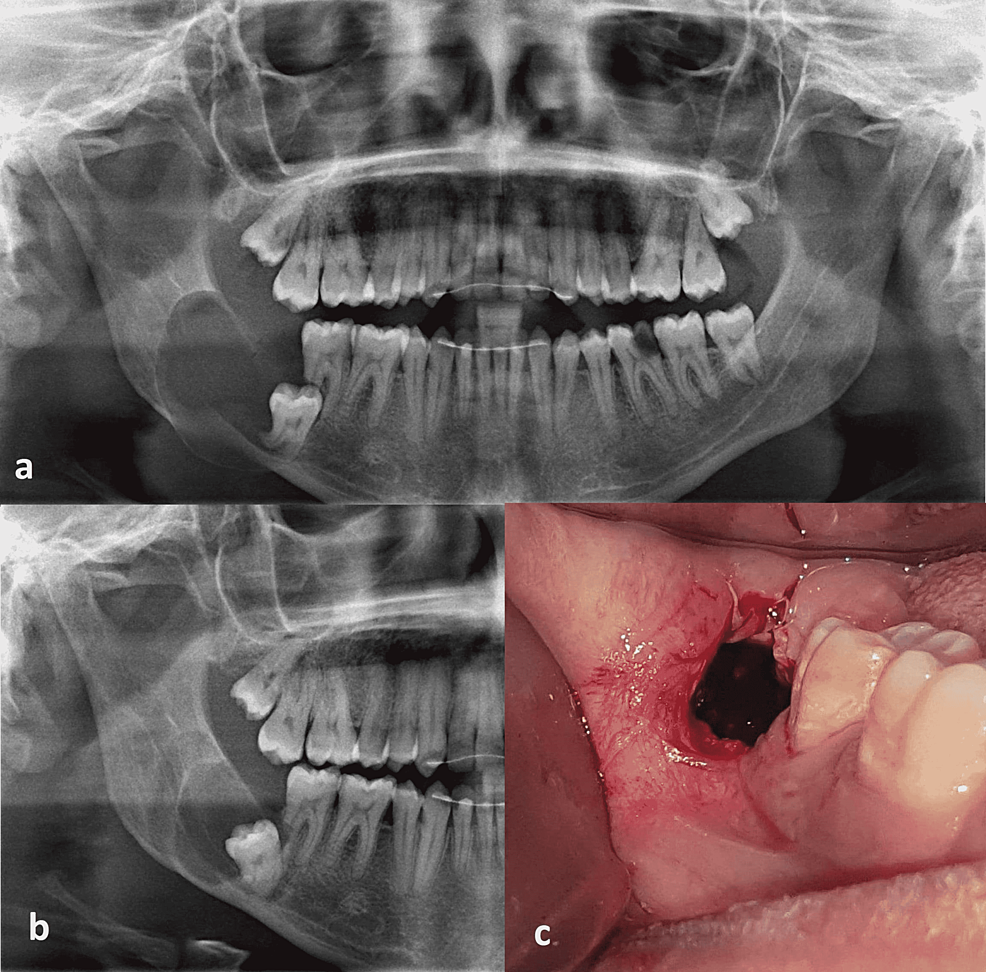

+ Giai đoạn sau : Khi nang đã to, biểu hiện bằng một khối u cứng làm phồng ngách lợi, hoặc cả rãnh mũi – má nhưng vẫn không đau, da- niêm mạc bình thường, nếu vị trí nang phía hàm ếch làm hàm ếch bị phồng. Khi nang tiếp tục to làm xương hàm bị tiêu và mỏng đi, khi đó sờ ở ngách lợi có dấu hiệu bóng bàn. X-quang có hình nang và răng ngầm thân quay vào lòng nang.

Nếu không phát hiện và điều trị kịp thời, nang dễ gây biến chứng bội nhiễm và nhiễm trùng, sau đó gây rò. Tuỳ vị trí nang mà có biểu hiện lâm sàng ở vị trí đó và đường rò có thể vào ngách lợi, hàm ếch hoặc ra ngoài da.

Duy nhất bằng phẫu thuật

Dù ở giai đoạn thầm lặng hay đã rõ, khi lâm sàng và X.quang cho chẩn đoán xác định thì chỉ định phẫu thuật nên được thực hiện ngay. Trong phẫu thuật phải lấy bỏ toàn bộ màng nang và răng trong nang, sau đó hoặc khâu kín, hoặc dẫn lưu. Có thể ghép xương tự thân hay bột xương đông khô đồng loại.